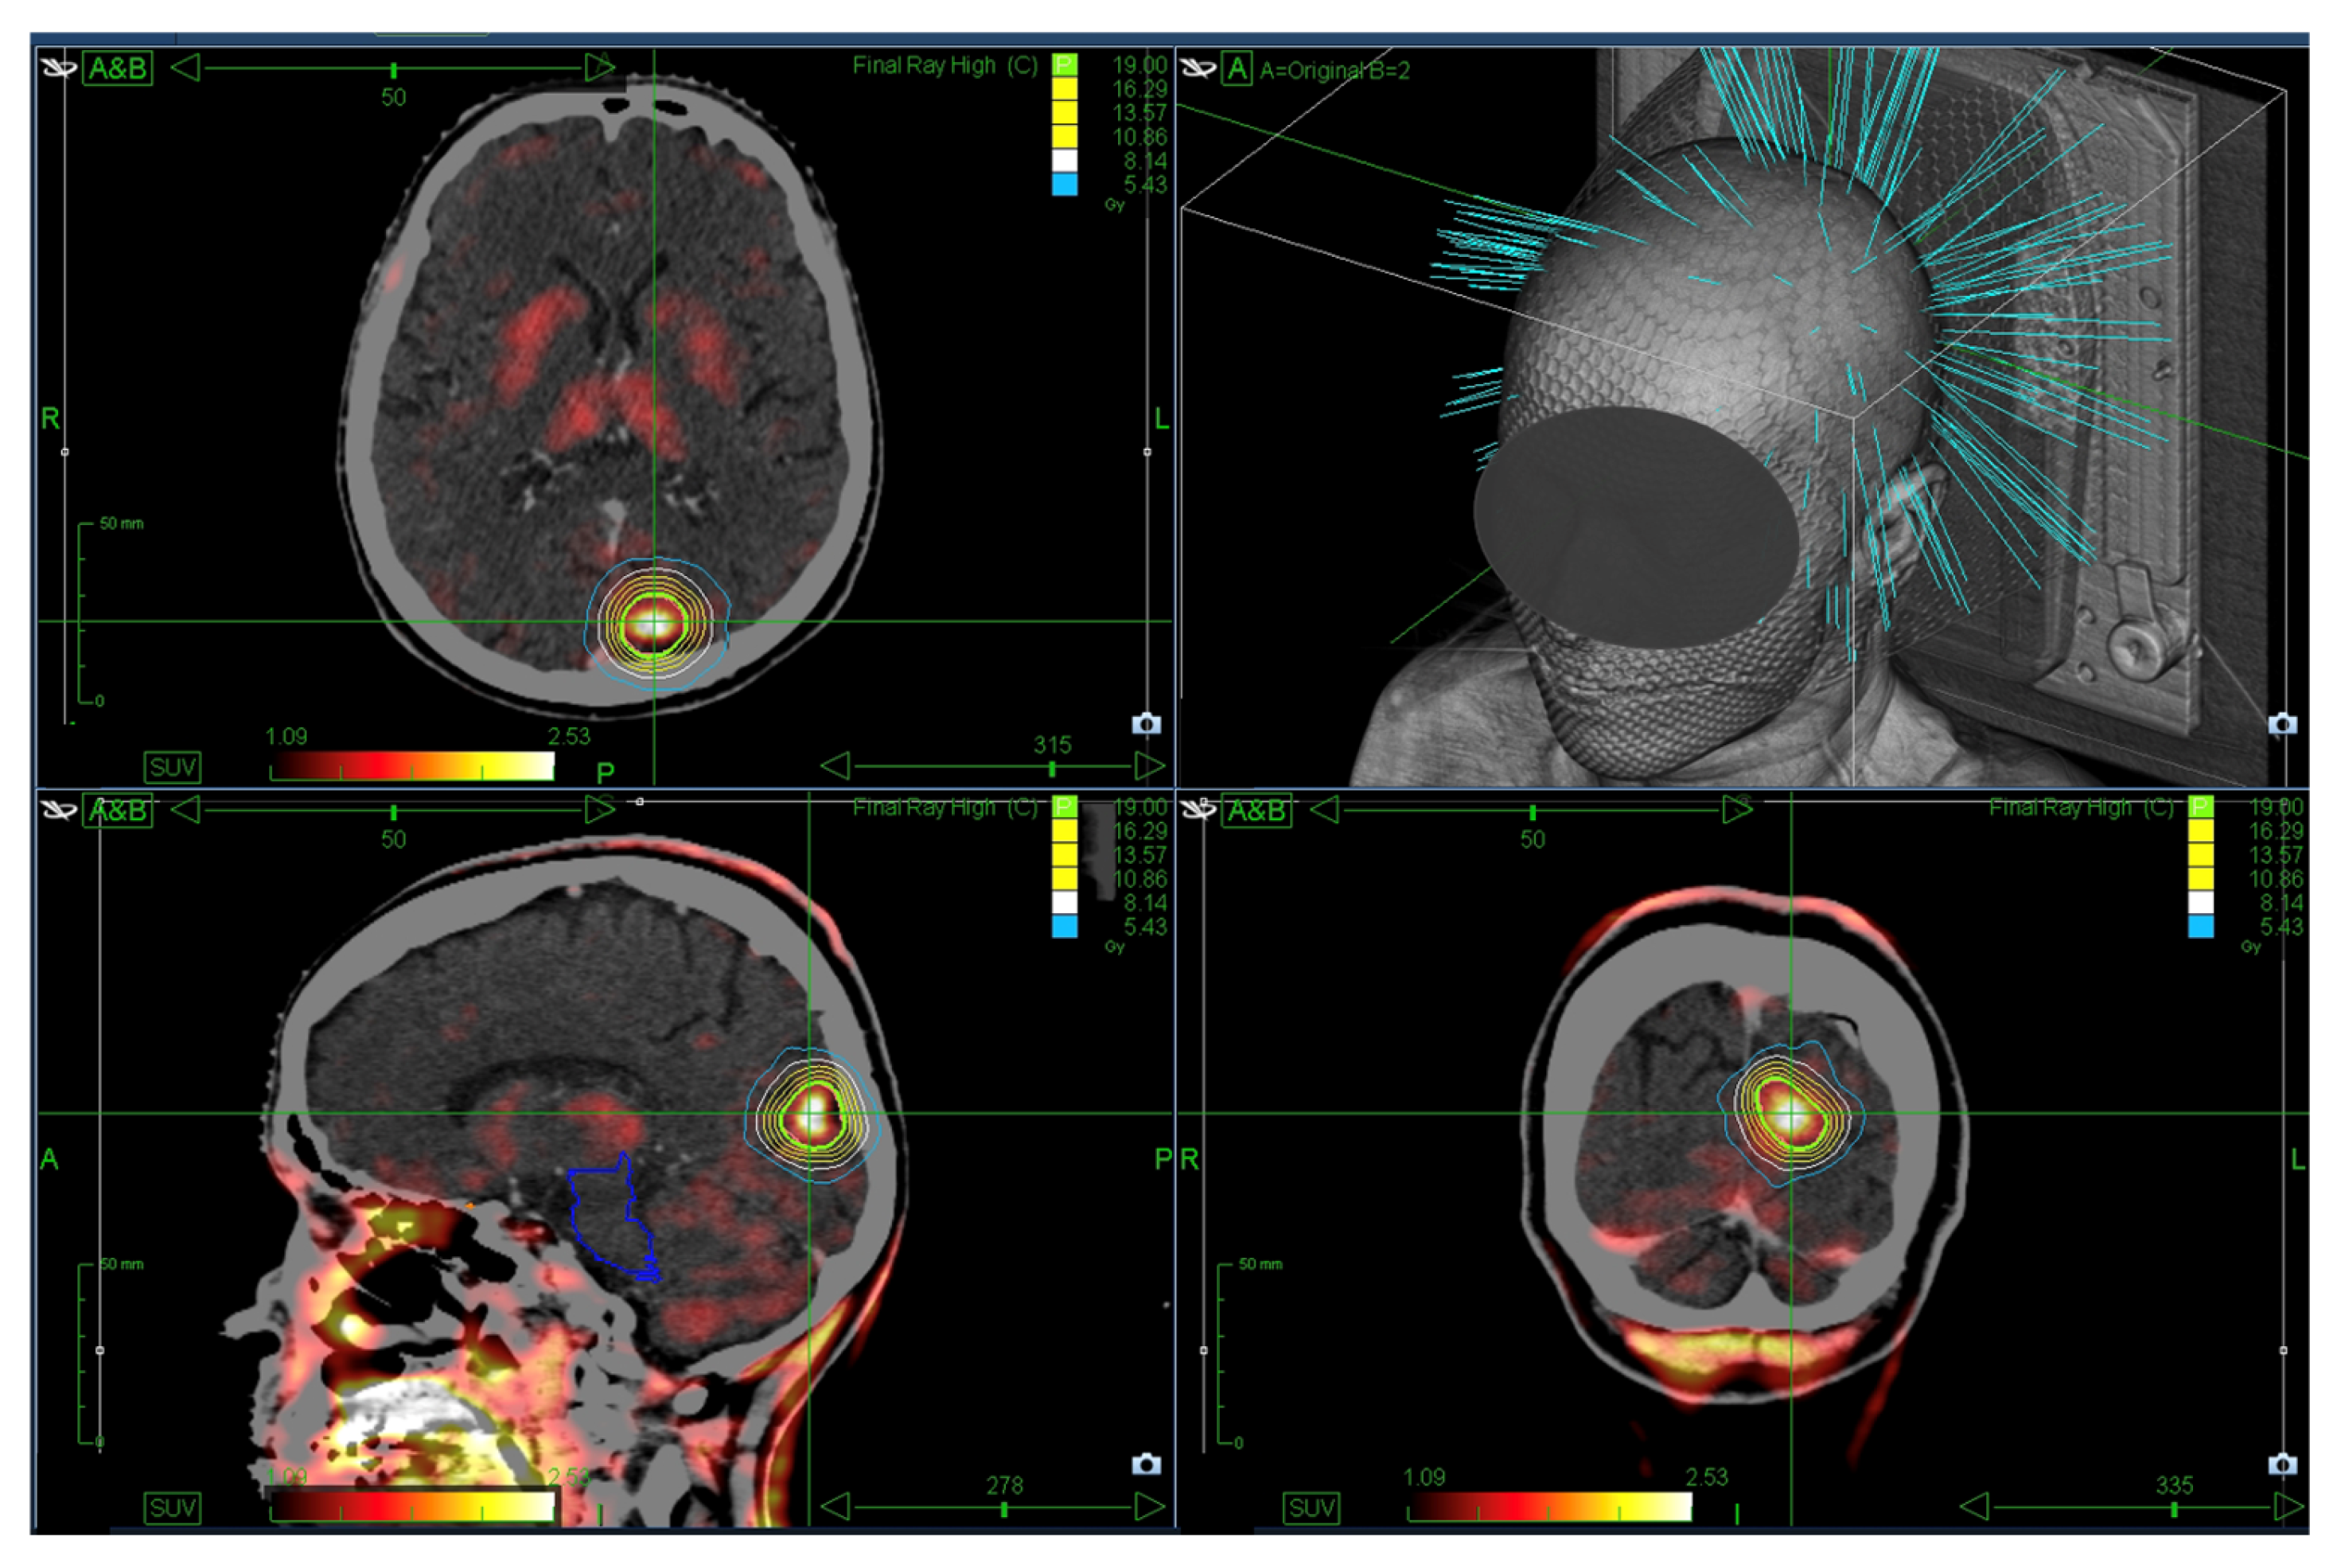

2.2. SRS Treatment

2.4. Simulation of AI-Based GTV Segmentation